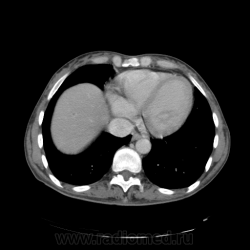

КТ ОБП - гепатомегалия, признаки панкреатита

МРТ ОБП - от 16.12.10 гепатомегалия, расширение панкреатических протоков.